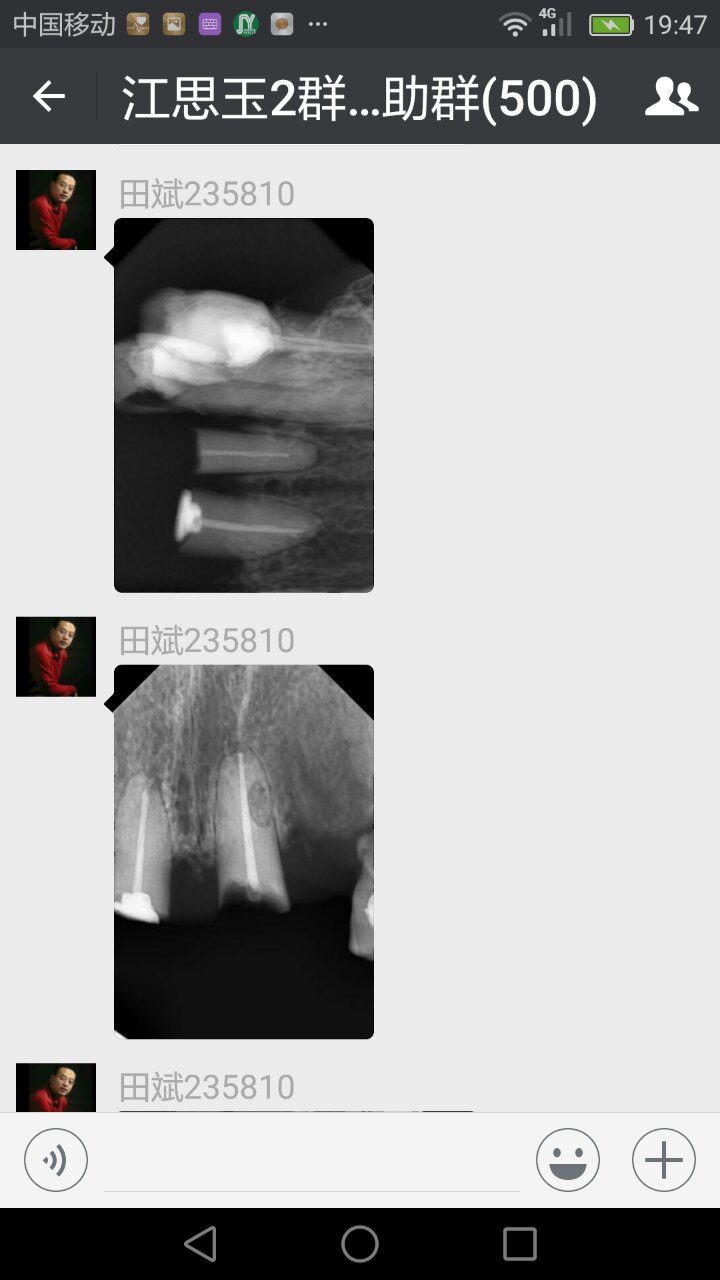

病例討論

整理江思玉群